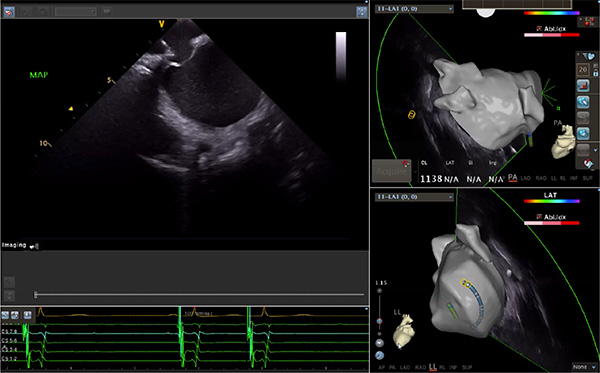

超聲心動(dòng)圖技術(shù)包括常規(guī)經(jīng)胸超聲(TTE)、經(jīng)食管超聲(TEE)、心腔內(nèi)超聲(ICE)、超聲聲學(xué)造影(MCE)、三維超聲心動(dòng)圖等,ICE是一種新興技術(shù)——將微型的換能器安裝在心導(dǎo)管的尖端,經(jīng)由外周血管輸送至心腔內(nèi)部,換能器發(fā)射聲波,對(duì)心臟及其鄰近組織進(jìn)行實(shí)時(shí)高質(zhì)量成像和(或)血流動(dòng)力學(xué)測(cè)定的超聲成像技術(shù)?;诓煌募夹g(shù)原理,心腔內(nèi)超聲導(dǎo)管被分為兩類(lèi):機(jī)械旋轉(zhuǎn)式超聲導(dǎo)管和相控陣超聲導(dǎo)管。目前,臨床上主要應(yīng)用的是相控陣超聲導(dǎo)管,ICE成像通過(guò)術(shù)者旋轉(zhuǎn)導(dǎo)管及操縱導(dǎo)管手柄上的兩個(gè)旋鈕來(lái)完成。

隨著心腔內(nèi)超聲的應(yīng)用更廣,性能也在逐漸優(yōu)化,已從二維成像轉(zhuǎn)變?yōu)?strong>三維成像,極大增強(qiáng)了引導(dǎo)及可視化能力。二維心腔內(nèi)超聲支持雙平面或三平面成像,可顯示兩個(gè)或三個(gè)不同的平面視圖,但醫(yī)生需將這些圖像在腦海中重新構(gòu)建為三維解剖結(jié)構(gòu)。三維心腔內(nèi)超聲則可直接呈現(xiàn)三維解剖結(jié)構(gòu)圖,便于醫(yī)生更輕松地開(kāi)展手術(shù)。按照產(chǎn)品發(fā)展方向,預(yù)計(jì)心腔內(nèi)超聲還將向更清晰、精準(zhǔn)、多功能等方向發(fā)展。